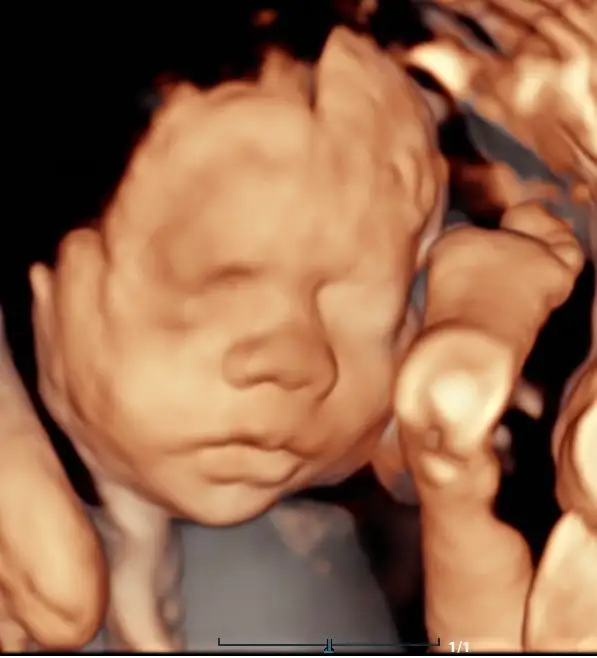

- 3D Ultrasound: Still, lifelike images of your baby’s face and body

- 4D Ultrasound: Real-time video of your baby moving, yawning, or smiling

- 5D HD Live Ultrasound: Enhanced clarity, lighting, and realism with true-to-life images

- Bonding Experience (28–36 weeks) – Capture detailed images of baby’s face and features